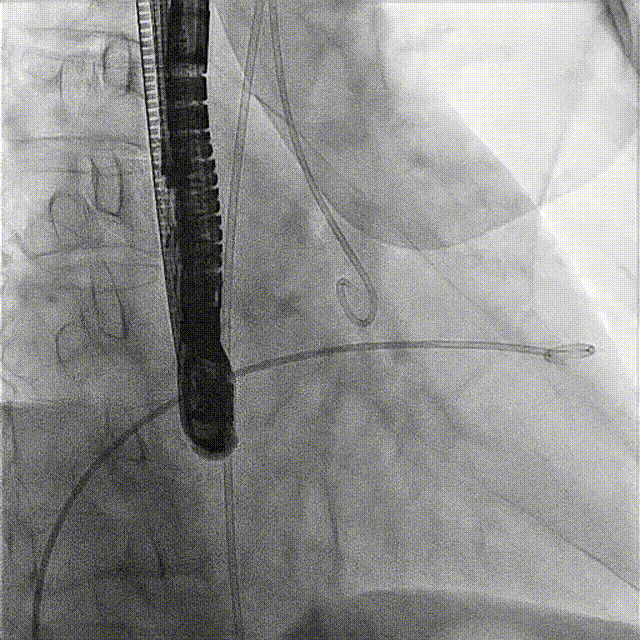

術(shù)前DSA

術(shù)前經(jīng)過全面系統(tǒng)的評估后,考慮患者存在高齡、心功能減低、三尖瓣瓣環(huán)重度擴張(三尖瓣極重度反流)等高危因素,因此廈心結(jié)構(gòu)心團隊聯(lián)合超聲心動、麻醉及護理團隊,制定了詳盡的圍術(shù)期治療方案及術(shù)中治療難點預(yù)案。術(shù)中,由王焱院長主刀,在蘇茂龍主任超聲心動團隊的輔助,上海市第一人民醫(yī)院陸方林主任的協(xié)助下,僅用時30分鐘,即順利完成了三尖瓣原位置換的手術(shù)。術(shù)中患者血流動力學(xué)穩(wěn)定,術(shù)后即刻顯示LuX-Valve Plus瓣膜位置良好,固定穩(wěn)定,瓣膜功能正常,無瓣周漏。